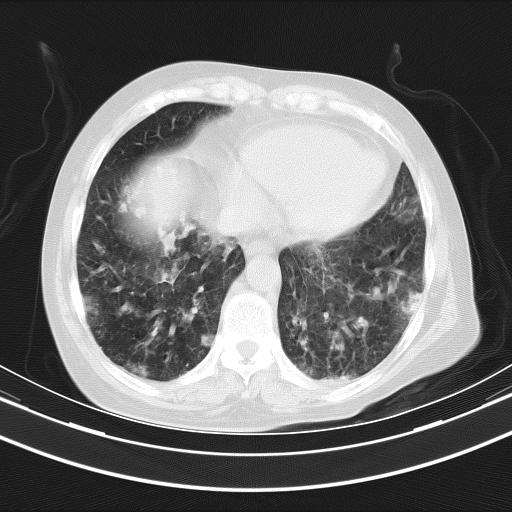

老年女性,嗜睡3天,意识模糊。轻咳,无发热。

双肺多发淡片影,毛玻璃影,,支持支气管肺炎,,建议血气找原因,,嗜睡是否肺性脑病?有没有慢支病史?

双肺炎症,建议抗炎治疗后复查,见过几个老年肺炎病例,没有发烧、咳嗽症状,直接以昏迷就诊。

1)两肺感染性病变;建议抗炎治疗后复查。2)纵隔淋巴结肿大。3)左侧胸腔积液。